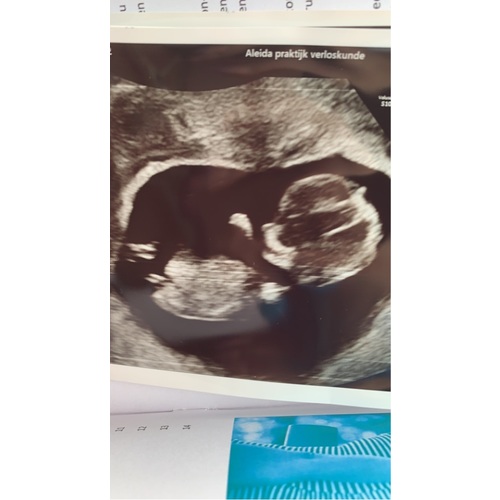

Je kan best al veel zien! Dit waren enkele plaatjes van mijn 12 weken echo. Ik was toen ook exact 12 weken zwanger

Wij zijn met 12 weken naar bovenmaas prenataal geweest (13 weken echo), en het was de beste ervaring ooit! Zou het iedereen aanraden. Je moet het wel zelf betalen (deze echo wordt vanaf juni dit jaar standaard via de vk), maar wij hebben alles kunnen zien al.

We hebben een uur mogen kijken en ze hebben de nekplooi gemeten, hartkamers gezien, hersenhelften, het niertje, de blaas, echt alles. Bizar! Ook kon de echoscopist toen al met 90% zekerheid zeggen wat het ging worden en bij 14+3 is dit bevestigd tijdens een geslachtsecho.

Hier een foto trouwens